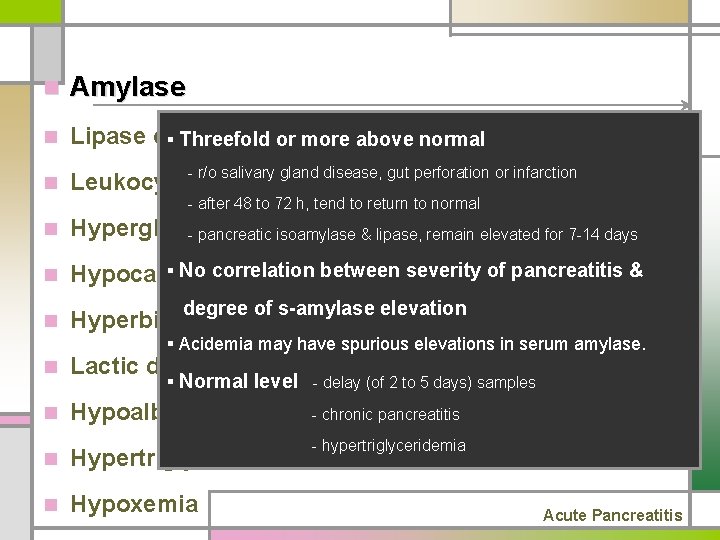

n Amylase n Lipase or§ Threefold trypsin or more above normal n - r/o salivary gland disease, gut perforation or infarction Leukocytosis, hemoconcentration with hematocrit - after 48 to 72 h, tend to return to normal n Hyperglycemia - pancreatic isoamylase & lipase, remain elevated for 7 -14 days n § No correlation between severity of pancreatitis & Hypocalcemia n Hyperbilirubinemia degree of s-amylase elevation § Acidemia may have spurious elevations in serum amylase. n Lactic dehydrogenase n Hypoalbuminemia § Normal level - delay (of 2 to 5 days) samples n Hypertriglyceridemia n Hypoxemia - chronic pancreatitis - hypertriglyceridemia Acute Pancreatitis